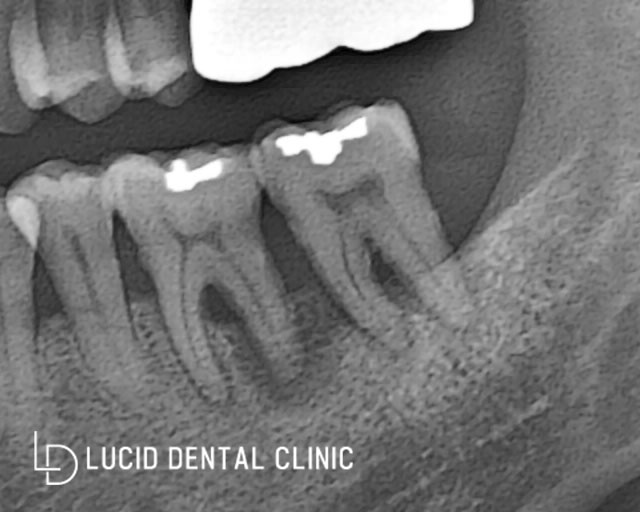

- 하악 좌측 어금니 (대구치)

해당 치아는 음식물 저작하는 데

중요한 기능을 하는 곳이기도 합니다.

대구치 2개 전부 골 소실로 인해

흔들리고 통증이 있다고 말씀하셨습니다.

치주 주위 조직이

뿌리도 잘 잡아주지 못하고

흔들리고 악취, 통증이 발생해

더 안 좋아지기 전에

치료해야겠다고 보여졌습니다.

- 하악 우측 어금니 (대구치)

대구치 한 개가 없으시기 때문에

위쪽을 심으면서 밑에도 같이 교합할 수 있게

한 개 심으면 좋겠죠?